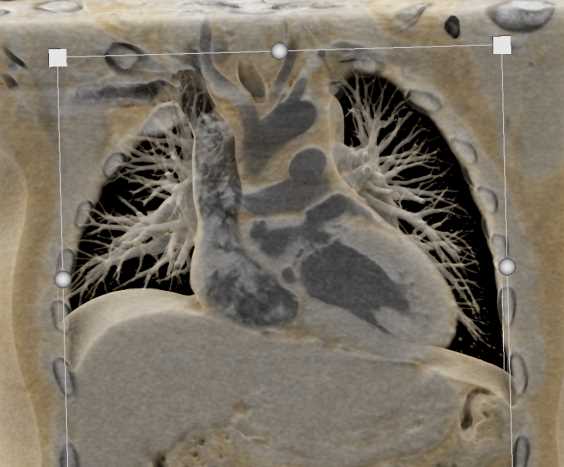

Diagnosis

Aortic Valve Repair